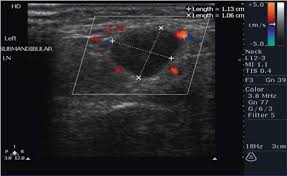

Air and bone also reflect sound waves. A lump in the neck —cancers that begin in the head or neck usually spread to lymph nodes in the neck before they spread elsewhere. A neck ultrasound may help diagnose (find): Breast ultrasound images are seen from superficial (skin) to deep (chest wall muscle) over a segment of tissue. A neck ultrasound can be used to observe the thyroid gland to look for nodules, growths, or tumors. But now i am worried that the reason the lump didn't show on the ultrasound is because it is actually under the skin in my neck (i.e in my throat) rather than on my actual thyroid/neck. David dang answered 14 years experience radiology node, cyst or others: A small lump on the neck usually is a lymph node, a small sebaceous cyst or a lipoma, although it could be something else. The most common symptom of thyroid cancer is a hard lump on the neck—but most patients experience no symptoms at all. This means that they are larger than about 1 centimeter (about 1/2 inch) across. Optimal positioning and exposure of the neck for ultrasound of the thyroid and parathyroid glands (a, b) and lateral neck for lymph node examination and mapping (c).while the vast majority of patients are supine on the exam table with a pillow supporting the shoulders to allow gentle neck extension, keep in mind that some patients have beautiful anatomy (d) that allows ultrasound exam even in. 1), and the presence of an echogenic hilus within lymph nodes was previously considered a sign of benignity. What does a healthy kidney look like on an ultrasound?

A small device called a transducer is moved over the area. Optimal positioning and exposure of the neck for ultrasound of the thyroid and parathyroid glands (a, b) and lateral neck for lymph node examination and mapping (c).while the vast majority of patients are supine on the exam table with a pillow supporting the shoulders to allow gentle neck extension, keep in mind that some patients have beautiful anatomy (d) that allows ultrasound exam even in. The camera remains attached either to a flexible tube called endoscope or to a probe, while it passes within an opening in your body, often your mouth. In the normal neck, about 90% of nodes with a maximum transverse diameter greater than 5 mm will demonstrate an echogenic hilus on high resolution ultrasound. Ultrasound an ultrasound is sometimes used, especially to look at the thyroid, salivary glands and lymph glands in the neck. A neck lump or nodule is the most common symptom of thyroid cancer. Should your doctor suggest that you undergo a neck ultrasound, you can be confident that your scan will be conducted by highly trained, experienced and caring sonographers. But now i am worried that the reason the lump didn't show on the ultrasound is because it is actually under the skin in my neck (i.e in my throat) rather than on my actual thyroid/neck.

If your cancer diagnosis is based on an ultrasound, it could easily be wrong. But ultrasound is usually the first choice for looking at the thyroid and neck structures. Other causes for a neck mass may be due to cancers such as lymphoma, thyroid or salivary gland cancer, skin cancer, or cancer that has spread from somewhere else in the body. Cancerous lymph nodes can occur anywhere on the neck and are typically described as firm, painless, and sometimes may be immovable. As thyroid cancer gets more advanced, you might notice symptoms like: Cancerous neck masses in adults are most often due to head and neck squamous cell carcinoma (hnscc). An ultrasound of the neck is used to examine the carotid arteries located on each side of a patient's neck. Optimal positioning and exposure of the neck for ultrasound of the thyroid and parathyroid glands (a, b) and lateral neck for lymph node examination and mapping (c).while the vast majority of patients are supine on the exam table with a pillow supporting the shoulders to allow gentle neck extension, keep in mind that some patients have beautiful anatomy (d) that allows ultrasound exam even in. On ultrasound, a breast cancer tumor is often seen as hypoechoic, has irregular borders, and may appear spiculated. And my neck look like an old shapai. The breast tissue kind of looks like waves on the ocean. But now i am worried that the reason the lump didn't show on the ultrasound is because it is actually under the skin in my neck (i.e in my throat) rather than on my actual thyroid/neck. In the framework of such terms as ultrasound of the neck, can be performed the following studies:

If a biopsy is needed, doctors use ultrasound to scan the area again, ensuring that they know exactly where to place the needle. In addition, the following tests may be used to diagnose head and neck cancer: And my neck look like an old shapai. A lump will form when a cancer cell infiltrates the capsule and multiplies. These are frequently seen in nodules containing papillary thyroid cancer. But ultrasound is usually the first choice for looking at the thyroid and neck structures. The normal neck contains scores of lymph nodes some of which are easily seen with ultrasound. Ultrasound an ultrasound is sometimes used, especially to look at the thyroid, salivary glands and lymph glands in the neck.